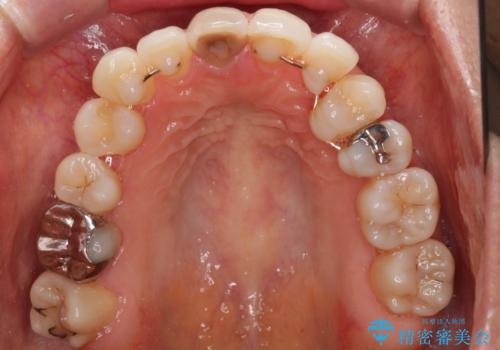

失活により変色した前歯 オールセラミッククラウンによる審美歯科治療

- 前歯の変色を気にして来院された患者様です。

ラミネートベニアによる治療を以前受けていたものの、神経組織が失活して以降、徐々に変色してきたとのことでした。

オールセラミッククラウンにて補綴治療を行うこととしました。